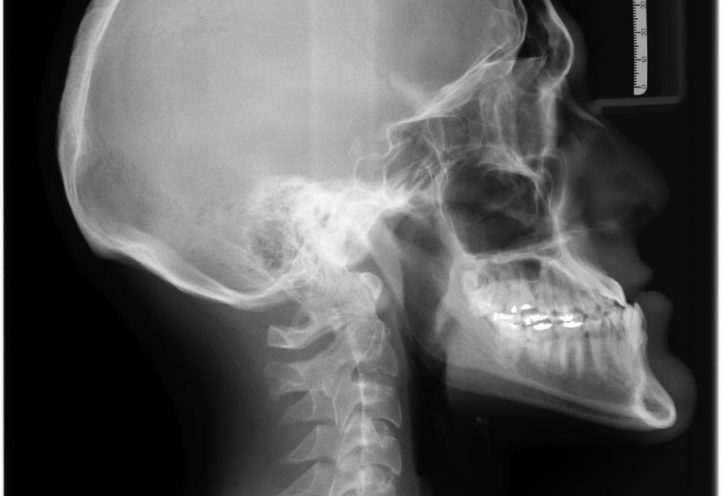

Røntgenundersøgelser er blandt de mest anvendte metoder til at diagnosticere forskellige medicinske tilstande. Disse undersøgelser er uundværlige, når det kommer til at opdage brud på knogler, forskellige typer af kræft, lungebetændelse og mange andre forhold. De virker ved at sende røntgenstråler gennem kroppen, som derefter afbilledes på en særlig film eller digitalt medium. Som et resultat opstår der billeder, hvor tætte strukturer som knogler fremstår hvide, mens blødere væv vises i nuancer af grå.